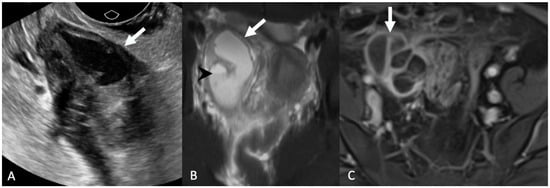

5.1.1. Hydrosalpinx and Hematosalpinx

5.1.3. Adnexal Ectopic Pregnancy

5.1.4. Adnexal Torsion

5.1.5. Paraovarian Cyst

5.1.6. Peritoneal Inclusion Cyst